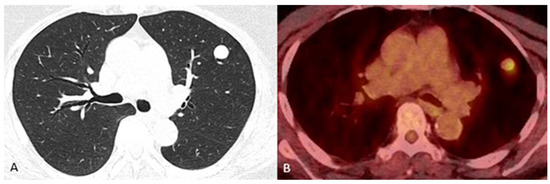

A Rare Case of Primary Pulmonary Meningioma

by Calista Sha, Leo Li, Fernanda Mitchell, Frank Breuer, Riona Park and Paul C. Lee

J. Clin. Med. 2025, 14(8), 2688; https://doi.org/10.3390/jcm14082688 - 15 Apr 2025

Background: Primary pulmonary meningioma (PPM) is an uncommon tumor originating in the lung. Although predominantly benign, there are instances of aggressive tumors exhibiting malignant features. Due to their rarity, our understanding of PPMs is primarily gleaned from case reports or small case [...] Read more.

Background: Primary pulmonary meningioma (PPM) is an uncommon tumor originating in the lung. Although predominantly benign, there are instances of aggressive tumors exhibiting malignant features. Due to their rarity, our understanding of PPMs is primarily gleaned from case reports or small case series. Methods: This report details the case of an 84-year-old female presenting with an incidental, well-circumscribed, enlarging nodule (1.4 × 1.3 × 0.9 cm) in the left upper lobe (LUL). Initial imaging found it to be highly suspicious of lung cancer. Results: Upon surgical resection, pathological analysis confirmed the tumor’s characteristics to be consistent with a benign PPM. Postoperative recovery was uneventful and there is no evidence of recurrence. Conclusions: Our report aims to contribute to the expanding body of knowledge concerning incidental PPMs by documenting our clinical encounter with this patient. Full article

(This article belongs to the Section Respiratory Medicine)

Show Figures

Figure 1